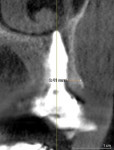

Achieving primary implant stability at the time of EITRT facilitates immediate temporization. As previously mentioned, tapered implants are often used instead of parallel-walled implants because of their ability to achieve a higher insertion torque and/or implant stability quotient (ISQ).17 Unfortunately, tapered implants are widest at the platform, complicating biologic considerations. Recently, a novel, inverted body design implant has addressed the issues of achieving adequate primary stability and increasing implant-tooth or implant-implant distances, as well as reducing proximity to the facial socket wall and increasing gap space.18,19 This implant has demonstrated the ability to achieve high levels of insertion torque, enable enhancement of thin facial bone, increase distances between the implant and adjacent teeth, and facilitate screw retention for temporary and definitive prostheses.20 In a 1-year multicenter study, this type of implant exhibited stable ridge contours, facial bone measurements of 1.5 mm to 2 mm thickness (Figure 3), and soft-tissue thickness of 3 mm when combined with a SAC implant design and dual-zone bone grafting for EITRT.21